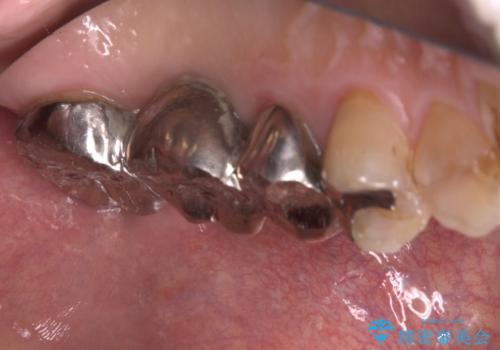

- 主訴:左上一番奥の歯の奥側にフロスを沿わせてこするといつも汚れがでてくる。

左上に保険適用の⑤ 6 ⑦ブリッジが入っており、7番目の歯と被せものとの境目に段差があり、そこに汚れが停滞したいたため適合の良いオールセラミッククラウンブリッジでのやり替えとなりました。

左上7番遠心マージン不適を認め、そこに汚れが停滞していたためやり替えをおすすめし、汚れが付着しずらく審美性に優れたセラミッククラウンブリッジでのやり替えとなりました。

保険適用のメタルインレーを除去したところ、ポンティック部の過度な加圧によって歯肉が強く発赤していたため、一度仮歯に置き換え歯肉の治りを待った後、適切な加圧強さのオールセラミッククラウンブリッジをセットしています。